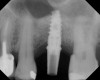

Because the bone grafting materials used in this technique need physical stability during healing to support the raised membrane, there is a high probability that significant shrinkage of the graft will occur as it heals and matures if only non-demineralized material is used. For these reasons, a composite graft using calcium sulfate, DFDBA, and mineralized particulate bone is used. A 50:50 mixture by volume of mineralized bone grafting material and DFDBA is used, to which approximately 40% calcium sulfate by volume is added. A higher percentage of calcium sulfate is used relative to that described for composite grafting in other uses, because some of the calcium sulfate will wash out during bone packing. Another advantage to this composite graft is that it is not as radiopaque as a purely mineralized graft. This allows radiographic monitoring of the bone healing around the implant, which can be used to time abutment placement on the implant. This is demonstrated in Figure 4 and Figure 5, which are radiographs taken on the day of the initial surgery showing the radiographic appearance of the composite graft, implant, and graft, and in Figure 6, a 5-month postoperative radiograph with the abutment in place. The old floor of the sinus is indistinguishable from the area of new bone. Figure 7 shows a CBCT scan (Carestream Dental, www.carestreamdental.com) taken at 4 months with the old floor of the sinus indistinguishable from the new bone formed.

The implant is then delivered and should be well stabilized in the bone. If there is any mobility of the implant, it can either be placed a little deeper (if there is enough native bone) or the implant can be removed and the procedure aborted, in which case it would be a two-stage procedure. This should rarely occur with the tapered designed implant, even with only 2 mm of native bone. Using a bone-level platform-shifting implant (or a tissue-level designed implant) is critical, as the hard and soft tissue will establish a biologic width. If an external hex type of implant is used and the shoulder is placed at the bone level, an expected bone loss of 1.5 mm to 2 mm will occur.24 Figure 10 shows proper bone-level implant depth placement with a platform-shifting design. In this case, a 3-mm healing abutment was placed at the time of surgery to avoid a secondary uncovering surgery, but an implant-level healing abutment could have been placed instead. As can be seen, there was only about 2 mm to 3 mm of native bone height. The membrane was raised about 8 mm to 9 mm. Comparing the radiograph on the day of surgery (Figure 10) to the 6-month postoperative radiograph (Figure 11) shows no loss of native bone, as well as the positive change in appearance of the grafted bone. The 3.5-month CBCT scan (Figure 12) shows good healing of the bone with no coronal bone loss. With minimal native bone present, as in this case, the use of a non-platform-shifting or non-tissue-level implant design could be problematic. After 1.5 mm to 2 mm of crestal bone loss, an external hex designed implant could develop instability with possible implant failure. If a non-tapered implant is used and bone loss occurs during healing, migration of the implant into the sinus could potentially occur. The surgeon can use either a healing abutment or implant-level closure screw over the implant shoulder. With patients who tend to use their tongues to explore or play with the area, or if the area is under a removable partial denture, a closure screw is recommended.

A 74-year-old male patient presented with about 4 mm to 5 mm of native bone in the No. 4 position (Figure 17). A composite graft, as described in Case 1, was used, as was the same implant type, but the implant was 11.5 mm in length with a taper of 5 mm to 4.2 mm. The approximately 16-month post-healed floor of the sinus was raised about 7 mm to 8 mm (Figure 18). The CBCT scan taken at 16 months postoperatively showed no change in appearance from the area of the old floor of the sinus to the new bone formed (Figure 19). Although it was endodontically involved, tooth No. 15 was not extracted, against professional advice. As can be seen in Figure 18, the No. 14 implant is acting as a bridge abutment.

This patient was a 73-year-old man with only about 3.5 mm of native bone in the No. 3 site (Figure 20). The composite graft used here was a 50:50 mixture of DFDBA and deproteinized bovine bone mineral (Osteohealth, www.osteohealth.com) with approximately 40% calcium sulfate added. The implant was the same type and length as in Case 1 above. Figure 21 shows the area on the day of placement. In the CBCT scan on the day of placement (Figure 22), the native bone and bone graft were clearly discernable. However, the postoperative radiograph taken at 6.5 months (Figure 23) showed no marginal bone loss and a significantly denser appearance than when the graft was place. The membrane was raised about 7 mm to 8 mm. The final radiograph was taken after extraction of tooth No. 2 and after extraction of tooth No. 4 and immediate implant placement.